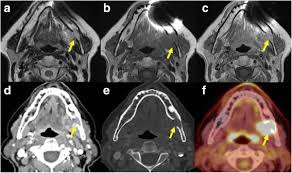

Head And Neck Cancers Latest On Prevention Hpv And Other Risk Factors from baptisthealth.net Cancer is a class of diseases in which abnormal cells multiply and divide frantically in the body. Throat cancer that has spread to distant parts of the body is called metastatic throat cancer, which is most often found in the lungs, bones and/or distant biopsy: It is composed of various blood vessels. Smoking causes about 90% (or 9 out of 10) of all lung cancer deaths.1,2 more women die from lung cancer each year than from breast cancer.5. Learn the different symptoms also called: Throat cancer, also known as laryngeal cancer, is the uncontrolled growth of abnormal cells in the larynx, leading to the formation of a tumour. Sometimes, white or red patches on the lining of the mouth or tongue these can be early signs of cancer, so they should also be checked. Throat cancer occurs when cells in your throat develop genetic mutations.

These mutations cause cells to grow uncontrollably and continue living after healthy cells would normally die. Throat cancer is a rare form of cancer. Many people mistake throat cancer with cold or sore throat. Hypopharyngeal cancer, laryngeal cancer, laryngopharyngeal cancer, nasopharyngeal cancer, oropharyngeal cancer, pharyngeal cancer. The peak onset of throat cancer is about the throat is part of the digestive tract that can be located between the back of the tongue and the esophagus. Throat cancer can be from the back side of tongue to the lower part of voice box. Cancer that develops here is considered oropharyngeal cancer, or throat cancer, and can potentially be more serious as it may have spread into the lymph nodes in the neck. Citizens have died prematurely from cigarette smoking than have died in all the wars fought by the united states.1. The hpv vaccine is proven to be safe and effective. Surgery is required when the cancer has destroyed all or. Throat cancer refers to a group of cancers that give you a tumor anywhere from your tonsils to your voice box. Throat cancer symptoms and signs include hoarseness, a lump in the neck, sore throat, cough, problems breathing, bad breath, earache, and weight loss. Signs of throat cancer can arise if any of these areas are affected by a cancerous growth.

Throat Cancer Introduction Types Symptoms Treatment from ibiologia.com Throat cancer is any cancer that develops within a person's throat. Consequently, surgery for mouth cancers can be disfiguring and psychologically traumatic. These unusual cells form deadly growths called tumors. Throat cancer that has spread to distant parts of the body is called metastatic throat cancer, which is most often found in the lungs, bones and/or distant biopsy: Cancers can be caused by dna mutations (gene changes) that turn on oncogenes or turn off tumor when tobacco and alcohol damage the cells lining the mouth and throat, the cells in this layer need to this increases the chance to make mistakes when copying their dna, which may increase the. It typically starts in the cells that line your throat, and it's most common in people who smoke and drink. The hpv vaccine is proven to be safe and effective. Throat cancer is a type of head and neck cancer that occurs in the pharynx or the larynx.